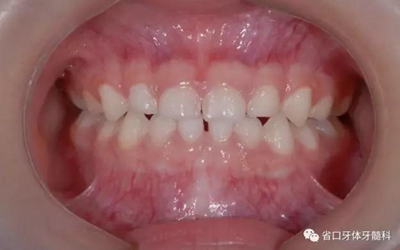

圖4 正面牙相(2015年1月)

5.jpg